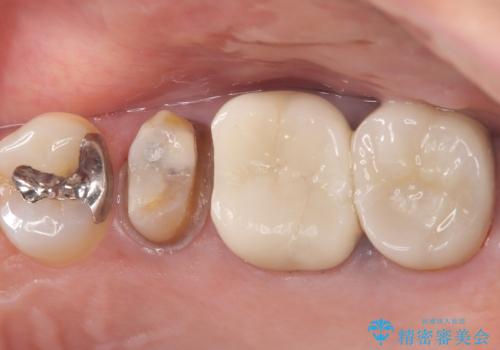

【セラミッククラウン】土台と被せものがズレている気がする

- 主訴:いつも物が詰まる場所があり気になる。衛生士に被せものと土台の境目に汚れが溜まっている箇所があると指摘され気になっている。

過去に入れた被せものと土台の歯との適合が悪く、隙間が出来ておりそこに汚れが溜まりやすい状態になっていました。セラミッククラウンでのやり替えとなりました。

唇側マージン不適なこと説明し、審美性・適合性に優れたセラミッククラウン(スタンダード)でのやり替えとなりました。

治療途中、一度仮歯に置き換えを行っています。